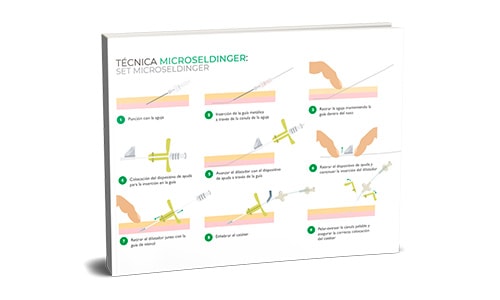

Infografía Canalización PICC neonatal con Técnica microseldinger: set microseldinger

Descarga la infografía sobre Canalización PICC neonatal con Técnica microseldinger: set microseldinger

Recomendaciones para realizar la técnica Seldinger Modificada en neonatos

La versión evolucionada de la Seldinger llamada Seldinger modificada (o Microseldinger o micropunción) consiste en tener un introductor que va a servir de guía para encaminar